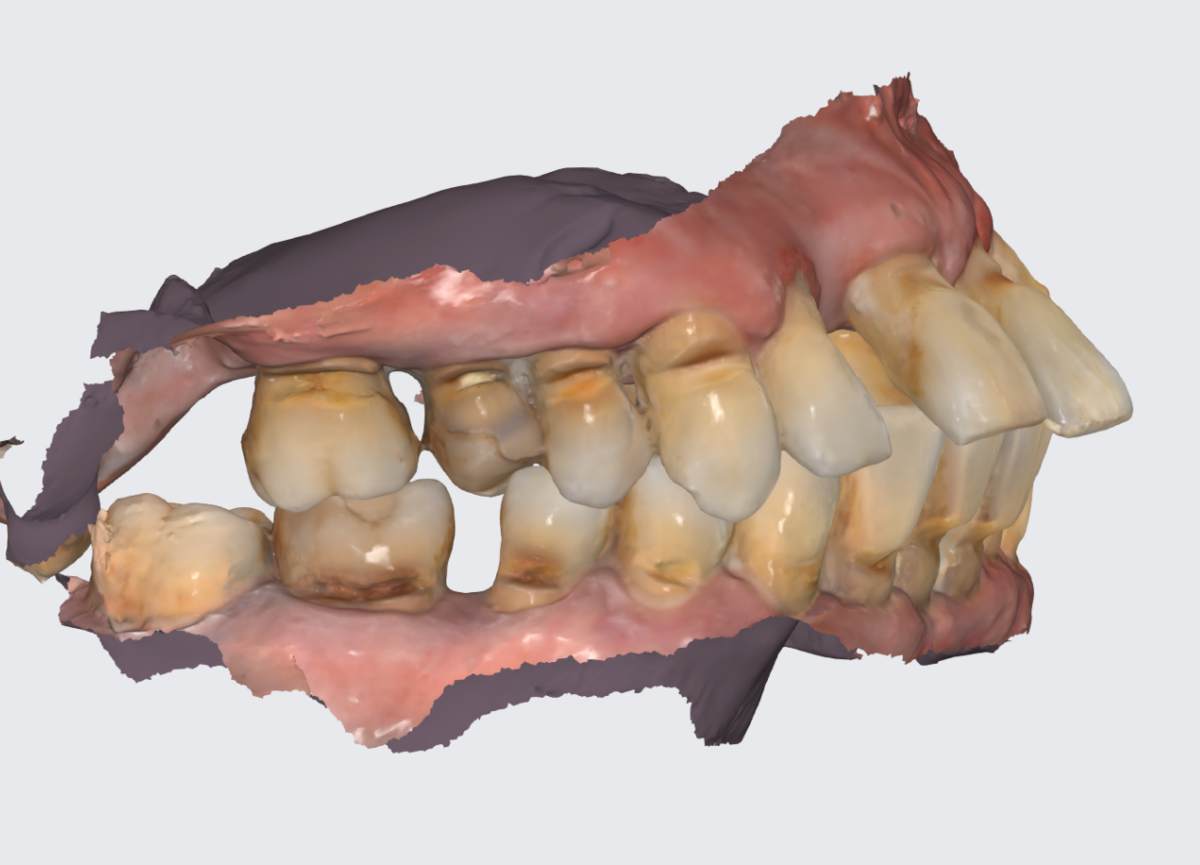

Цифровой слепок верхней челюсти.

Задача - восстановить жевательную эффективность во втором сегменте верхней челюсти.

Кажется, что всё просто.

Проблемная зона.

Вот почему зубы нужно удалять:

Зубы обозначены номерами без привязки к классификации.

1 - объёмная вкладка, которой очень много лет. Постоянно выпадает, от стенок зуба ничего толкового не осталось.

2 - корень, от которого ничего не осталось и он не пригоден для восстановления.

3 - зуб выдвинулся, наклонился. Имплантату с коронкой этот зуб будет мешать, не получится адекватной гигиены и велики риски потерять конструкцию. Но пациент не готов к расставанию. Не настаиваем.

4 - кариес корня в таком объёме и в такой локации, что шансов у зуба не остаётся.